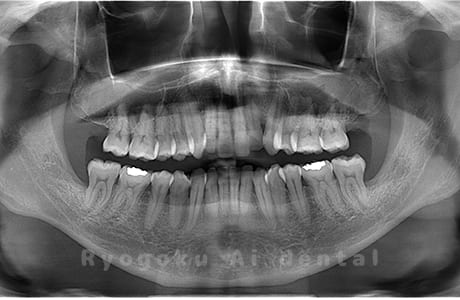

Case04

-

- 原因

- 上顎の親知らず、下顎の水平埋伏の親知らず

- 治療内容

- 上顎の親知らず、下顎の水平埋伏の親知らずを抜歯したケースです。

<リスク・副作用>

手術後は痛み、腫れ、痺れなどの副作用が生じる場合があります。